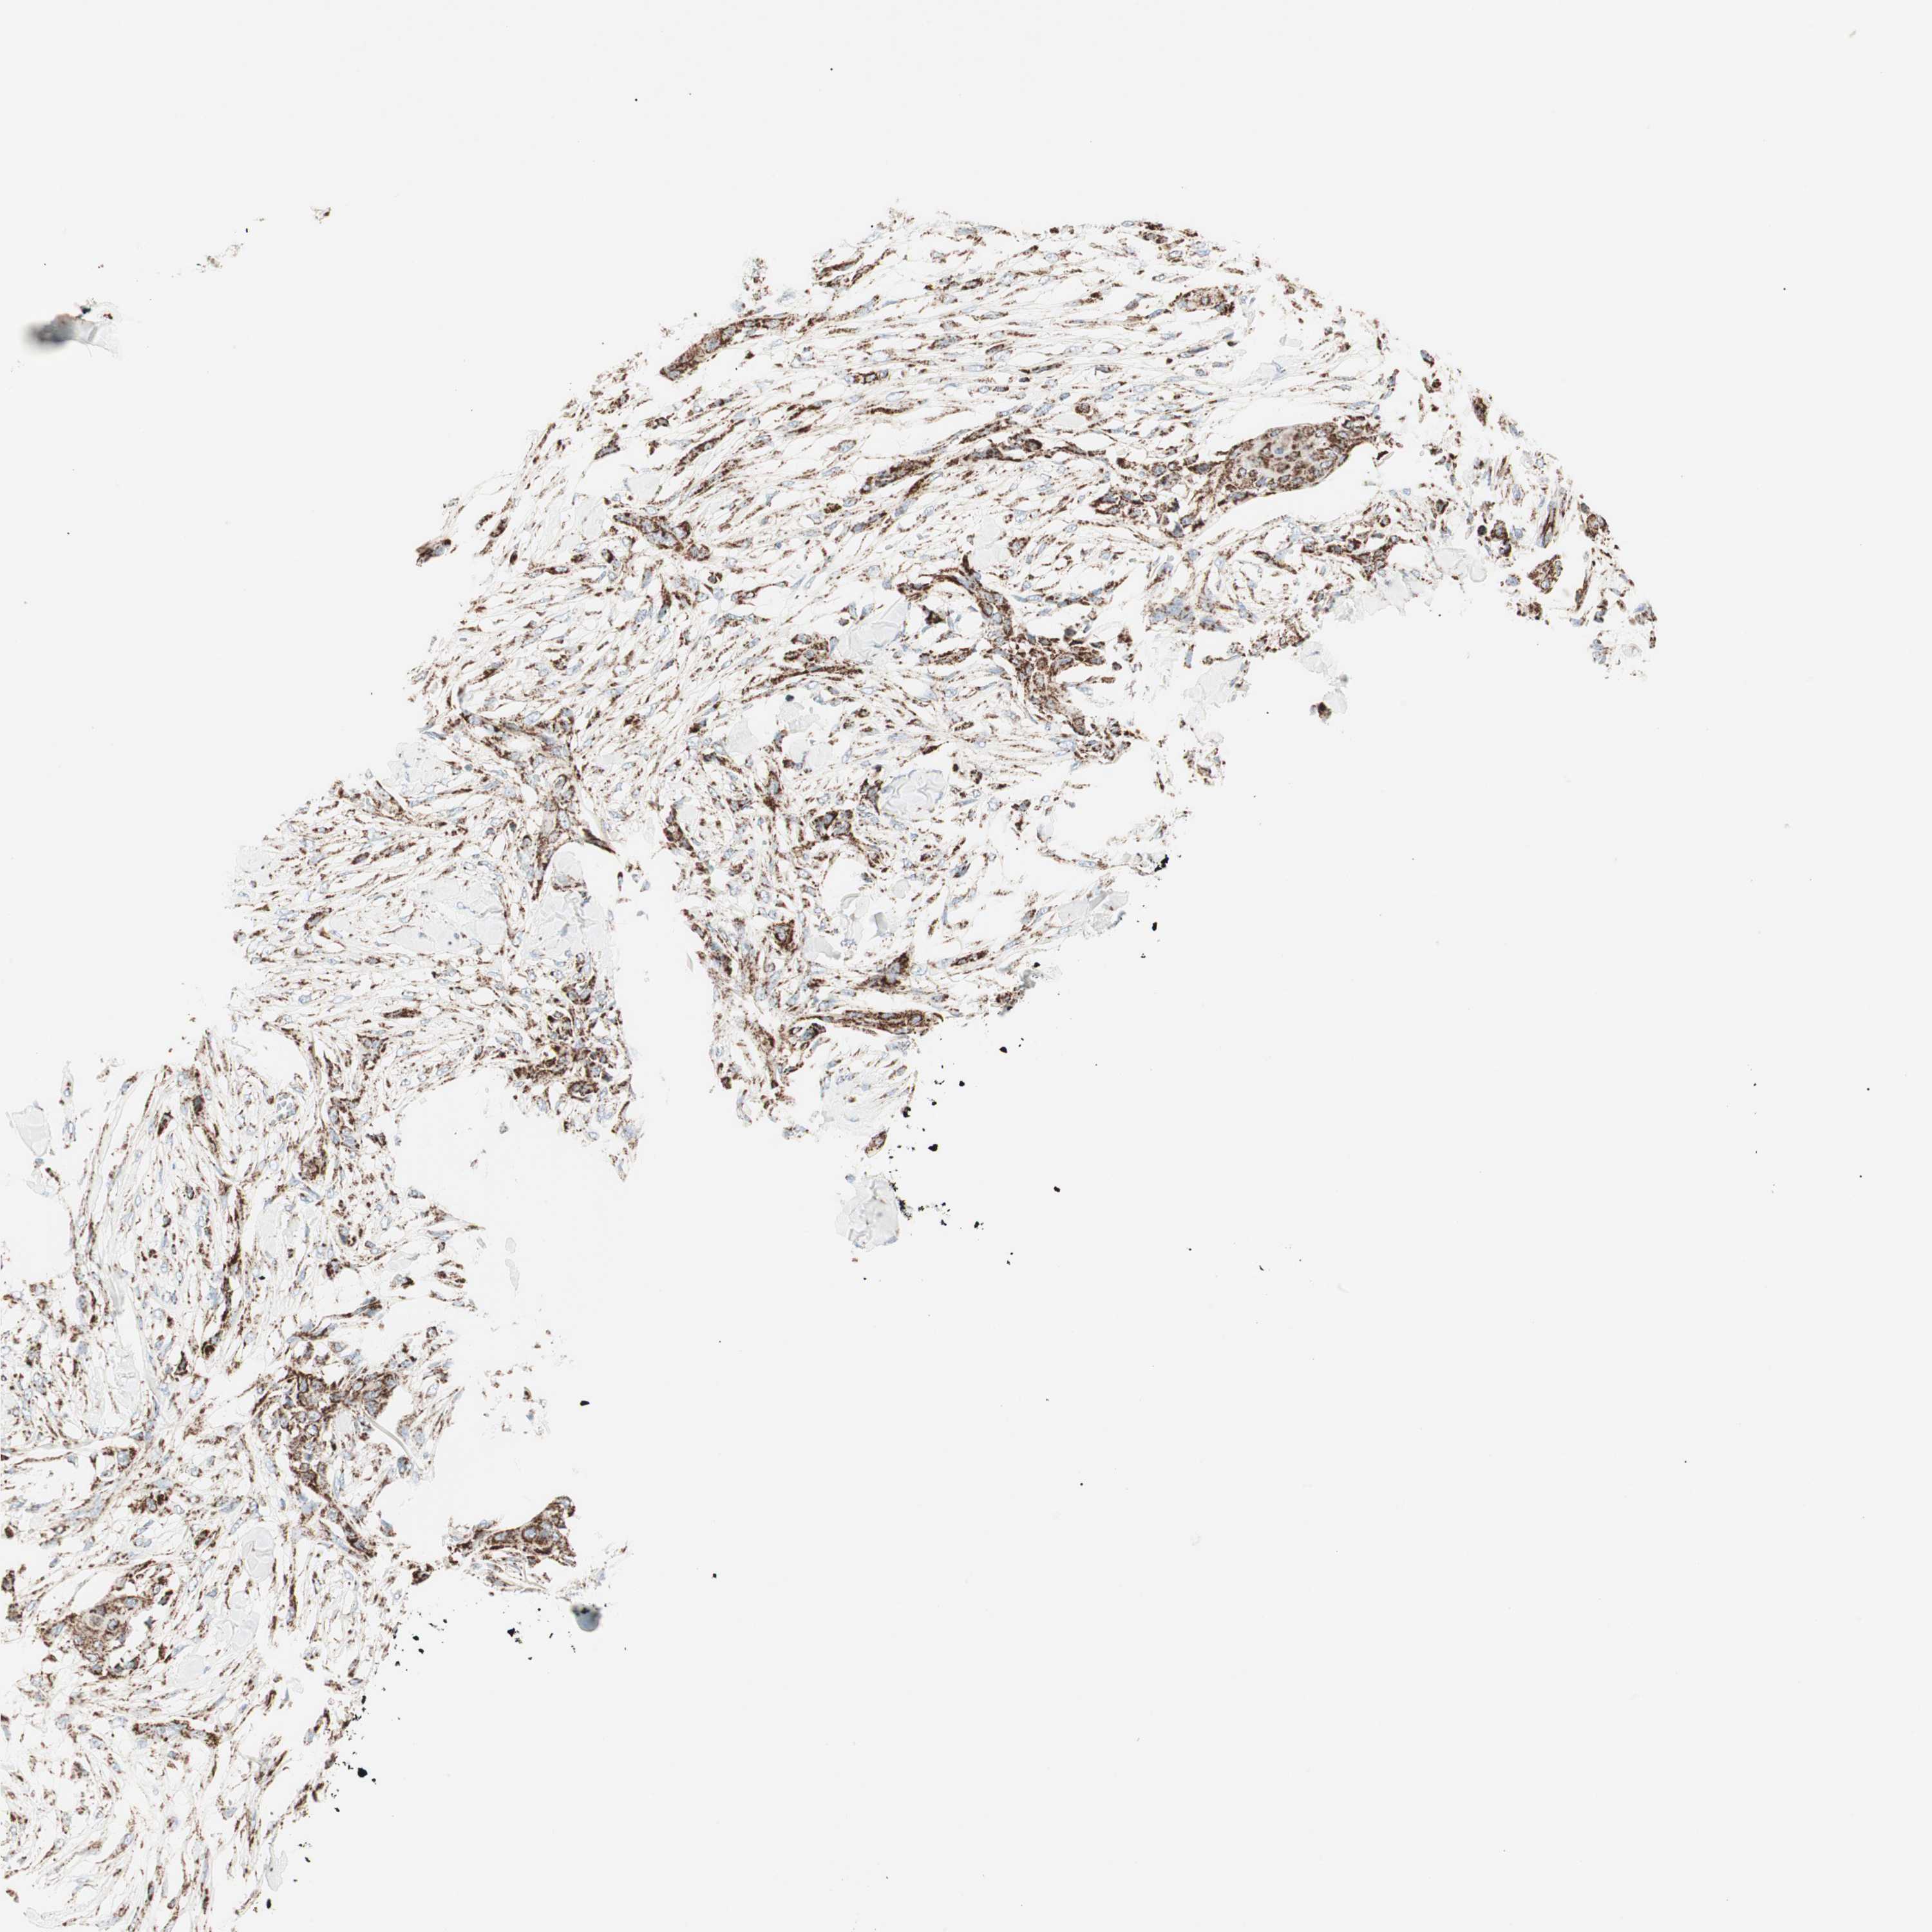

SKIN CANCER - Protein expressioni

A mouse-over function shows sample information and annotation data. Click on an image to view it in a full screen mode. Samples can be filtered based on level of antibody staining by selecting one or several of the following categories: high, medium, low and not detected. The assay and annotation is described here.

Antibody stainingi

Antibody staining in the annotated cell types in the current human tissue is reported as not detected, low, medium, or high, based on conventional immunohistochemistry profiling in selected tissues. This score is based on the combination of the staining intensity and fraction of stained cells.

Each image is clickable and will lead to virtual microscopy that enables deeper exploration of all samples and also displays staining intensity scores, fraction scores and subcellular localization as well as patient and tissue information for each sample.

Antibody HPA011562

Squamous cell carcinoma, NOS